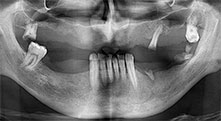

Bratu: Utilizamos los insertos de forma rutinaria para la extracción de injertos óseos y la ranuración de las crestas alveolares. También utilizamos las Piezomed B6/B7 para practicar osteotomías en dientes retenidos y no retiramos implantes que pueden conservarse. Todas estas son indicaciones que requieren cortes profundos y limpios.

Bratu: Preferimos realizar las osteotomías en la línea oblicua externa de la cara posterior del maxilar inferior, y no en la región situada entre los orificios. Tras realizar una incisión en los tejidos blandos, utilizamos las nuevas sierras para definir el contorno de la osteotomía. De este modo, conseguimos una preparación completa en prácticamente el 80 por ciento de los casos. Por otro lado, en algunas ocasiones también utilizamos otros insertos piezoquirúrgicos, así como un cincel para mover el injerto. Para nosotros, esta es una técnica de intervención muy eficaz.

Bratu: Considero que la piezocirugía constituye un gran salto hacia delante en cirugía oral. Gracias a esta técnica, las preparaciones óseas resultan más sencillas y ligeras. Además, se pierde menos hueso, por ejemplo, en las extracciones. Este aspecto es muy importante en la zona estética, sobre todo cuando se ha planeado realizar un implante inmediato. Del mismo modo, la piezocirugía también es una apuesta segura para los tejidos blandos. Gracias a ella, las lesiones en la membrana del seno maxilar, así como las lesiones nerviosas cuando se realizan extracciones de injertos óseos, son prácticamente cosa del pasado. También hay datos que demuestran que se producen menos inflamaciones y molestias postoperatorias. Dicho sea de paso, la piezocirugía también permite preparar muy bien los tabiques de los senos maxilares. Y, por supuesto, no hay que olvidar que nuestros pacientes se ven beneficiados por la menor agresividad de esta técnica.